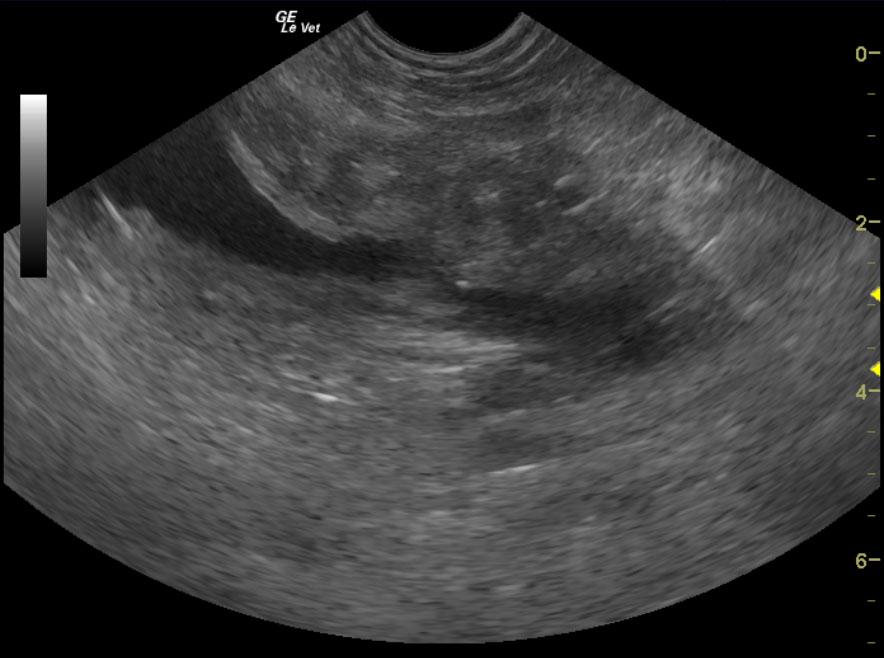

A 9-year-old intact female Brittany Spaniel dog, with previous history of cystotomy, was presented on emergency at a 24-hour facility for vomiting, shaking, painful abdomen, and extreme lethargy. Physical examination found the patient whining and crying, depressed, with tacky mucous membranes, and a firm distended abdomen. The patient was ambulatory but was most comfortable in sternal recumbency. Abnormalities on CBC and blood chemistry included leukocytosis, increased BUN, and mild hypoalbuminemia. Coagulation panel was within normal range.

A 9-year-old intact female Brittany Spaniel dog, with previous history of cystotomy, was presented on emergency at a 24-hour facility for vomiting, shaking, painful abdomen, and extreme lethargy. Physical examination found the patient whining and crying, depressed, with tacky mucous membranes, and a firm distended abdomen. The patient was ambulatory but was most comfortable in sternal recumbency. Abnormalities on CBC and blood chemistry included leukocytosis, increased BUN, and mild hypoalbuminemia. Coagulation panel was within normal range. Survey radiographs showed generalized loss of detail (consistent with free fluid) and a linear radiodensity in the cranial abdomen. Despite being a poor surgical candidate, the patient was recommended for immediate exploratory surgery due to concern of a ruptured pyometra.